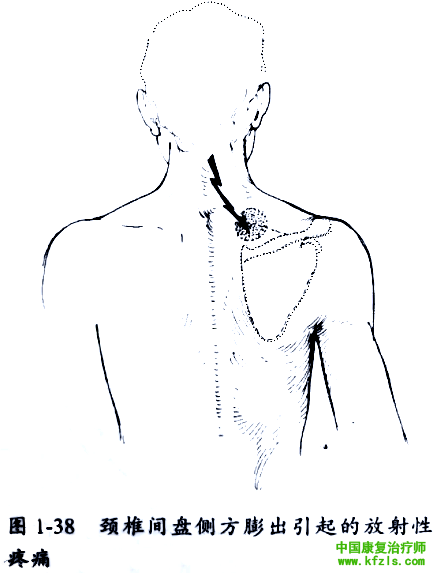

而椎间盘膨出但未完全突破纤维环时可能引起背部中央靠近肩胛骨内上部疼痛(图1-38)。侧方膨出则引起沿肩胛骨嵴部的疼痛(常见在内上角部),可伴随上臂的根性痛,但通常没有神经功能障碍。